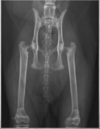

What are nutrient foramens?

A

Foramens superimposed on medullary cavity.

Fractures aren’t symmetrical so if the exact same mark is in the same spot in both limbs, consider nutrient foramens.

In the image: the thin dark lines. There is also a Mach line to the left of the nutrient foramen.